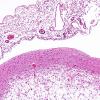

DEVELOPMENTAL MALFORMATIONS

Crossed Cerebellar Atrophy